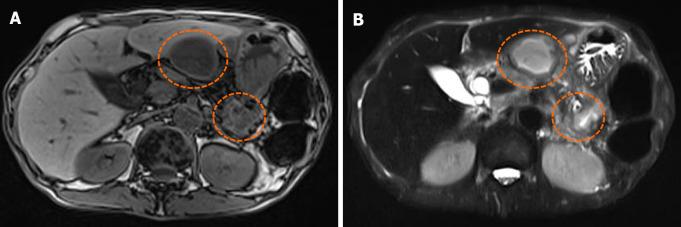

A 62-year-old male with a 10-year history of chronic pancreatitis presented with epigastric pain for one week and a 20 kg weight loss over one year. Computed tomography showed stones in the pancreas (mainly the head), expansion of the main pancreatic duct, and thinning of the pancreatic parenchyma. Magnetic resonance imaging showed infected pancreatic cysts connected to the stomach with a fistula from the splenic hilum to the caudal portion of the liver's lateral segment. An endoscopic retrograde pancreatography was performed; the guide wires could not pass through the stones in the pancreas and therefore, drainage of the main pancreatic duct was not achieved. Next, a distal pancreatomy and splenectomy were performed; however, the pancreatic juice in the remaining parenchyma was blocked by the stones. Hence, we performed a retrograde pancreatojejunostomy and Roux-en-Y anastomosis. The patient had no postoperative complications and was discharged from the hospital on postoperative day 14.

一名62岁男性,有10年慢性胰腺炎病史,出现上腹部疼痛1周,1年内体重减轻20公斤。计算机断层扫描显示胰腺(主要是头部)有结石,主胰管扩张,胰腺实质变薄。磁共振成像显示感染性胰腺囊肿与胃相连,脾门至肝外侧段尾状部有瘘管。进行了内镜逆行胰胆管造影;导丝无法穿过胰腺内的结石,因此未实现主胰管引流。接下来,进行了胰体尾切除术和脾切除术;然而,剩余实质内的胰液被结石阻塞。因此,我们进行了逆行胰空肠吻合术和Roux-en-Y吻合术。患者术后无并发症,术后第14天出院。